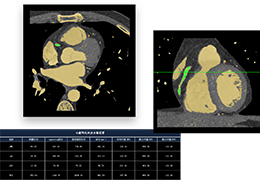

成像智能。

Eclipse 成像智能功能提供强大的处理能力和最佳质量的影像,同时减少质量错误并提高剂量效率。

凭借 AI、专有算法和先进的影像处理能力,提供出色的影像质量和无与伦比的诊断信心。

分析智能。

这些功能利用数字控制面板分析运营、业务和临床绩效。

使管理员能够跟踪关键参数,包括平均曝光率、拒绝的影像和探测器统计信息。

帮助确定需要改进的方面,支持为员工和部门制定适当的改进计划。